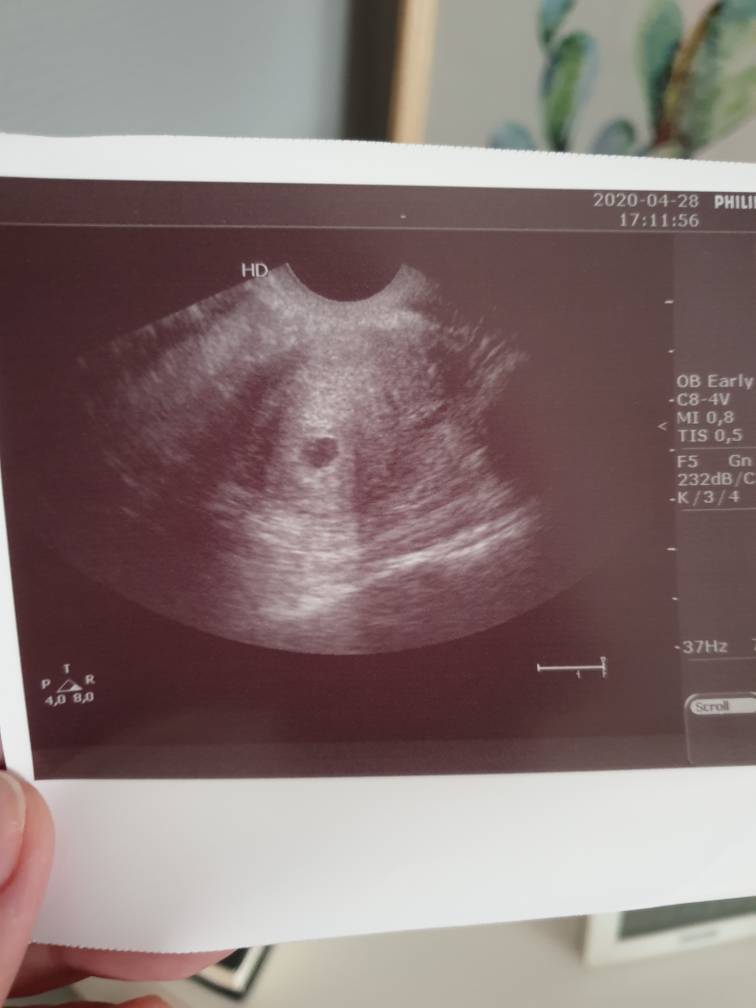

"a nikomu nie powiesz?". No i zrobiła, jest ciąża. Pęcherzyk z ciałkiem żółtym, na zdjęciu nie widać nic poza pęcherzykiem ale widziałam na monitorze. Niestety nie zmierzyła nic ani nie zapisała w systemie więc nie wiem który dokładnie tydzień i dzień. Powiedziała że 5-6 tydzień. Wydrukowała jedno zdjęcie i mówi "ja Ci usg nie robiłam i nigdy nie dostałaś tego zdjęcia" [emoji23]

Zobacz załącznik 1112693